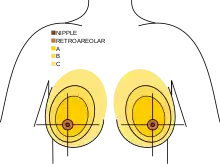

| An illustration of breast cancer | |